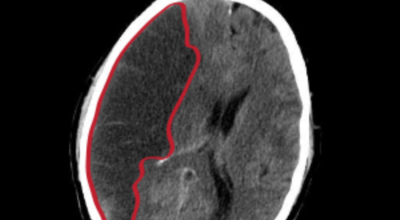

막힌 혈관으로도 혈액이 공급되긴 하나 혈관이 막혀있어 혈액을 보내긴 하나 제대로 흐르지 못하고 혈액이 쌓이고 축적되어 물풍선에 물이 꽉 차서 터지듯 뇌혈관이 터지는 경우가 일어날 수 있는데 이를 뇌출혈 이라고 해요. 물론 외상으로 인한 뇌출혈도 있지만 이처럼 뇌경색으로 인해 혈관이 막혀 터지는 경우도 있어요.

큰 뇌혈관이 막힌 경우라면 발생한지 4시간 반 안에 정맥 내로 혈전 용해제를 투여해 막힌 혈관을 뚫어주게 되고 6시간 이내라면 직접 동맥 내 시술을 통해 혈관을 막은 혈전을 직접 제거하는 혈전제거술을 시행하게 되는데요.